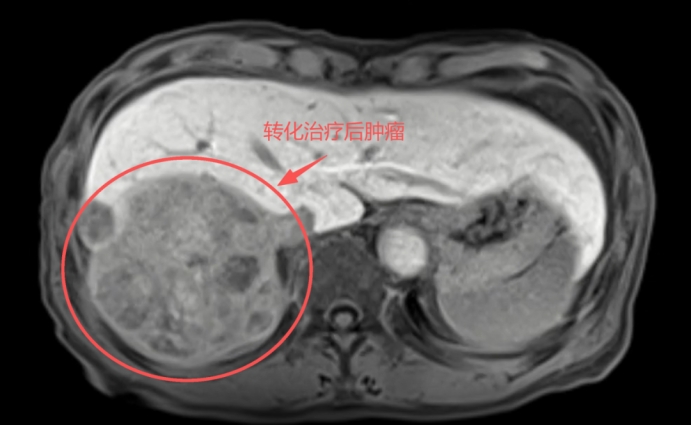

肿瘤显著缩小:肝右叶巨大肿瘤明显缩小,从173mm×124mm×142mm缩小到108mm×90mm×84mm,活性明显降低。

癌栓基本消失:门静脉右支癌栓退缩,主干癌栓基本消失。

健康肝脏“长大”:预留的左半肝体积从30%增生至53.4%,达到了安全手术标准。

转化治疗后肿瘤左半肝体积占比缩减到46.6%